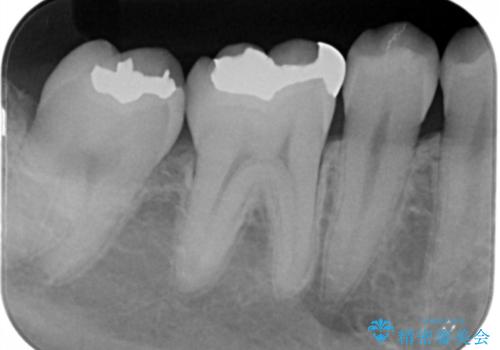

- 右上下6番の銀歯のやり変えを希望された患者様です。

切削量・形態を考慮し、上はセラミッククラウン、下はセラミックインレーでの治療を選択しました。

上はう蝕が歯頚部まで達していたのでクラウンでの治療を選択しました。

銀歯直下もう蝕が進行していたので全て除去した上でCRにて裏層しています。

下はクラウンほど切削量が多くないと判断し、インレーでの治療を選択しました。